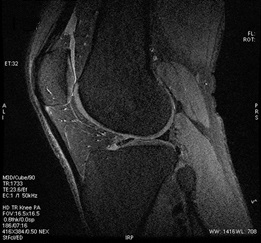

Figure 1. Knee example with User CV 12 set to 30 degree flip angle

- A smaller flip angle reduces image blurring with a tradeoff of reduced SNR.